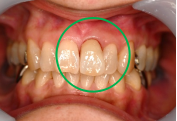

女性 Aさん 50代 (オールセラミック冠)

主訴

色が変わった上前歯をきれいにしたい。

治療内容

根管治療をし、オールセラミック冠を被せました。

所感

神経が取り除かれ、大きく詰め物がされていました。詰め物及び歯自体が変色し、虫歯になっていました。根管治療をし、ファイバーコアを入れ、オールセラミック冠を被せました。自分の歯は、捻転していましたが、被せ物により歯並びを改善することができました。

オールセラミック冠1本:¥104,500(税込)